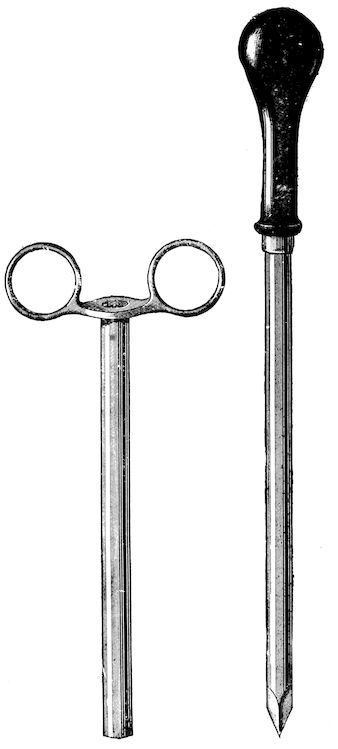

| Crushing foreign bodies in the œsophagus | 735 | |||

| Œsophagotomy | 736 | |||

| Sub-mucous dissection of the foreign body | 736 | |||

| Rumen | 737 | |||

| Puncture of the rumen | 737 | |||